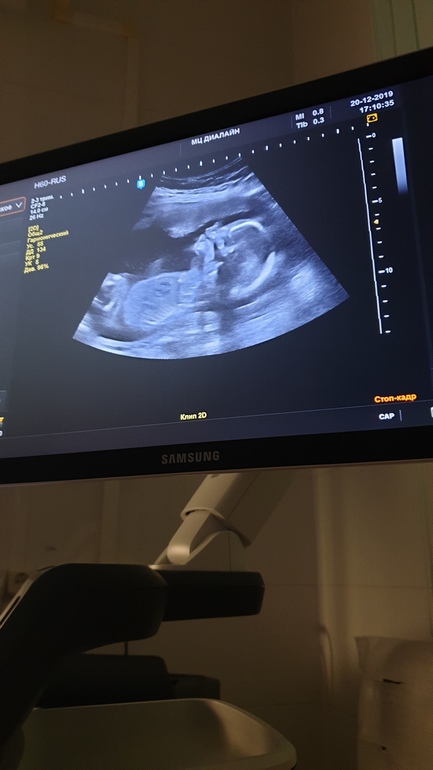

Пол малышаТак надеялась что дочку в этот раз зачали...И ощущения совсем другие.Но вот в 18 недель вердикт узиста - точно мальчик.Фото прилагаю.Посмотрите, пож- та!🙏Кому ошибались на таком сроке?..Муж сказал, что теперь только на внучку надеяться..🙈🤷♀️

На фото не видно, кто там.

Интересно по какому такому месту вы это определили😂😂😂это фото вообще не для определения пола.Там нет полового бугорка и мошонки по которым можно определить пол.

Я вот уже тоже весь инет облазила - если мальчик, то более белым должны быть выделены яички и сам ствол.( как косточка) а тут не понятно...

Тут согнутая нога-это очевидно.(также кости таза,бедра попали в боковой проекции);)Ну хочется кому то видеть половой член-ради бога😉Если узист и определил мальчика,то явно не с этого ракурса,а это фото сделал лишь на память и не более того!

На этом фото пол ребенка не видно.

Фото не показательно, сходите в нормальную клинику на узи с низу пусть посмотрят

По фото не понятно кто.

Ну на фоне белого кружка, что вы обаели, только наверно узист и пазглядит! Обычно делают фото снизу, между ног или кофейное зернвшко или сосиска 😂😂😂😂 у моих мужиков сосиска была уже с 13 недель! Там да, было очевидно... На вашем фото не понятно ничего

Хороший малышастик😍, по этому фото пол не определить, да и рано вам еще на внучек надеяться, вот мне уже можно😁